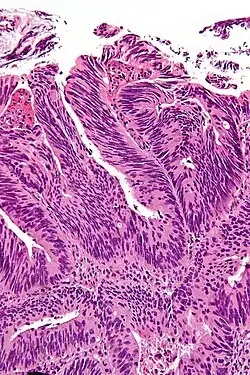

La marge chirurgicale désigne la présence de tissu cancéreux au contact des limites encrées de la partie enlevée lors de la résection[1]. L'analyse des marges chirurgicales contribue à établir un pronostic fiable pour l'évolution future du cancer et le risque de récidive[2]. Le statut des marges chirurgicales dépend notamment du stade d'évolution du cancer[3],[4].

Une marge chirurgicale positive signifie que le chirurgien a coupé au travers de la tumeur. Une partie de la tumeur est donc toujours présente chez les patients qui présentent alors un risque de récidive élevé.

Une marge chirurgicale négative signifie que la tumeur a été correctement retirée et que du tissu sain est présent tout autour de la tumeur[5]. Le chirurgien a donc coupé à distance du cancer. Ce type de marge n'est possible que si la tumeur ne s'est pas étendue.

On parle de marge R0 si la section chirurgicale passe à distance de la tumeur en laissant une marge plus ou moins épaisse de tissu sain[6].

Une marge chirurgicale positive est associée à un risque de récidive du cancer. Cependant, il peut persister des cellules tumorales également dans le cas d'un marge négative et donc un risque de récidive. La longueur de la marge chirurgicale, c'est-à-dire de l’affleurement de tissu cancéreux, est corrélée au risque de récidive : plus elle est petite et plus le risque est faible.